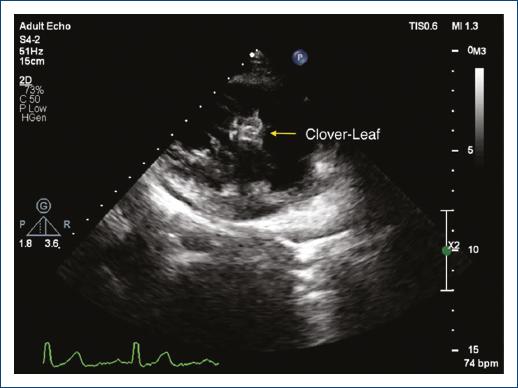

A 25-year-old woman presented to our echocardiography laboratory for a follow-up imaging study. She had a history of muscular ventricular septal defect (VSD) closure by Amplatzer Muscular VSD Occluder (St. Jude Medical, USA) 4 years before this visit. Since this repair, she has remained asymptomatic and was on no medication. In transthoracic echocardiography, the double disc device was visualized in apical four-chamber view (Fig. 1) with no residual VSD flow. Interestingly, in off-axis view of parasternal long-axis imaging, the device was visualized in the form of two side-by-side figure of 8 “Clover-leaf” appearances (Figs. 2 and 3).

Figure 3/Video 3 The occluder device resembles a clover-leaf in this off-axis parasternal long-axis view.

Percutaneous disc occluders due to their specific “epitrochoidal” mesh configuration and the interaction with ultrasound waves; form this image artifact when viewed from a coronal imaging position1. Transthoracic echocardiography is the main method of follow-up for post-procedural device position, and accurate interpretation of views is of utmost importance2.

By increasing utilization of percutaneous closure devices for various indications including atrial and VSD, left atrial appendage, patent foramen ovale, recognition of this particular pattern as a normal imaging artifact of a deployed double-disc device when visualized from a coronal imaging position is necessary to avoid misinterpretations of studies such as malposition or displaced device.